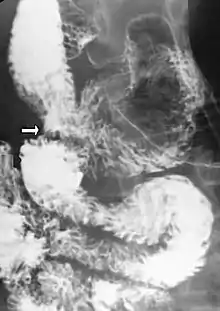

Upper gastrointestinal series showing extreme duodenal dilation (white arrow) abruptly preceding constriction by the SMA.- Ultrasound showing SMA syndrome[19]

Diagnosis is can be difficult, and usually one of exclusion. SMA syndrome is generally considered only after people have undergone an extensive evaluation of their gastrointestinal tract including upper endoscopy, and evaluation for various malabsorptive, ulcerative and inflammatory instestinal conditions with a higher diagnostic frequency. Diagnosis may follow X-ray examination revealing duodenal dilation followed by abrupt constriction proximal to the overlying SMA, as well as a delay in transit of four to six hours through the gastroduodenal region. Standard diagnostic exams include abdominal and pelvic computed tomography (CT) scan with oral and IV contrast, upper gastrointestinal series (UGI), and, for equivocal cases, hypotonic duodenography. In addition, vascular imaging studies such as ultrasound and contrast angiography may be used to indicate increased bloodflow velocity through the SMA or a narrowed SMA angle.[13][14]